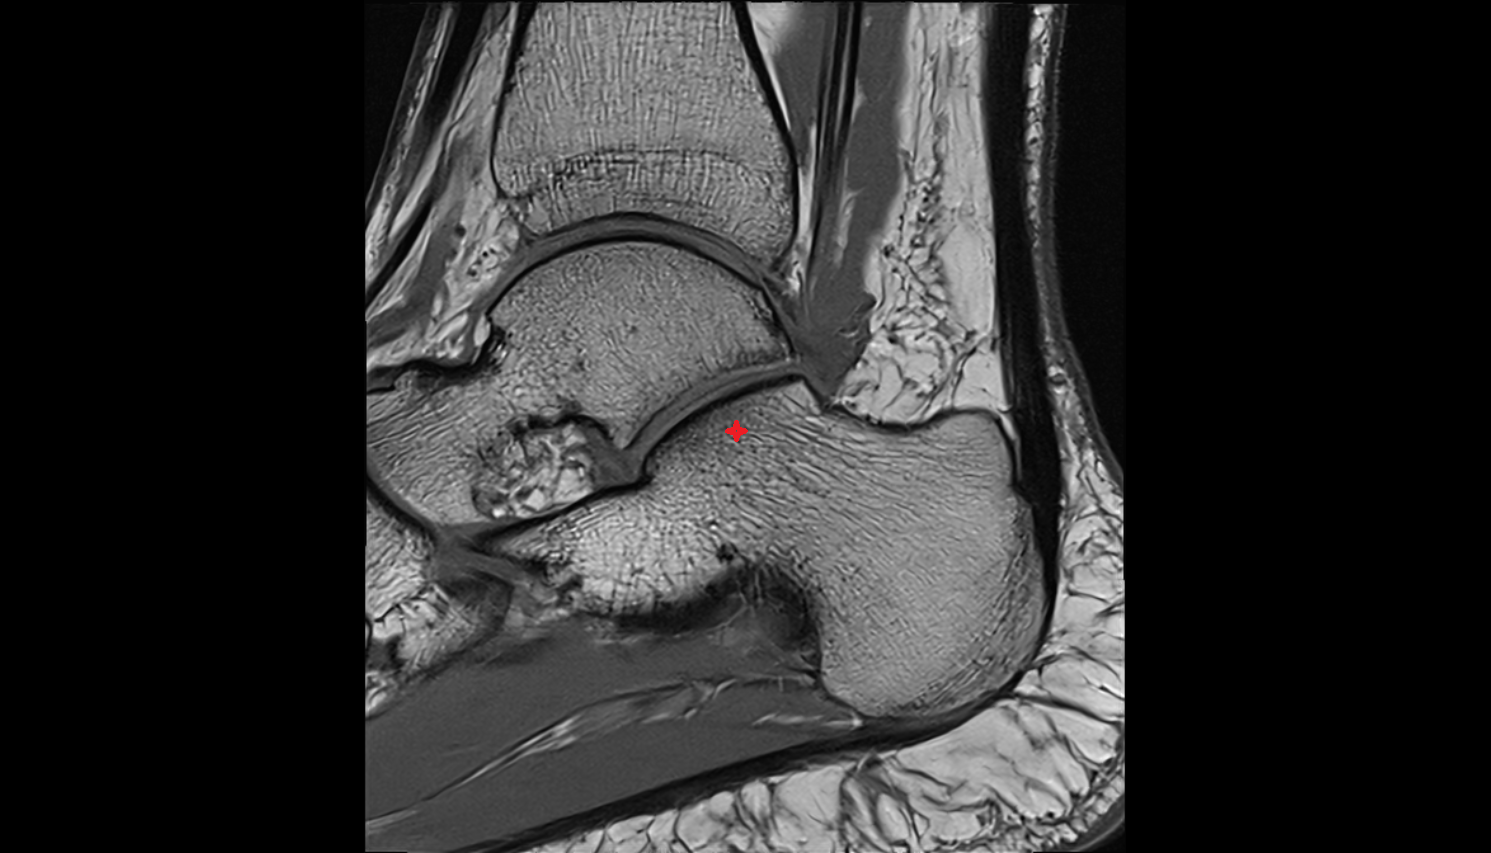

- Talus

- Head of talus

- Body of talus

- Neck of talus

- Calcaneus

- Ankle joint

- Talocalcaneal joint